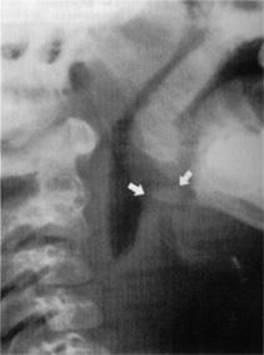

See Figure 12-2.

FIGURE 12-2. Radiograph of lateral soft tissue of neck demonstrating epiglottitis.

Note the thickening of the epiglottic and ariepiglottic folds (arrows). (Reproduced, with permission, from Schwartz DT, Reisdorff BJ. Emergency Radiology. New York: McGraw-Hill, 2000: 608.)